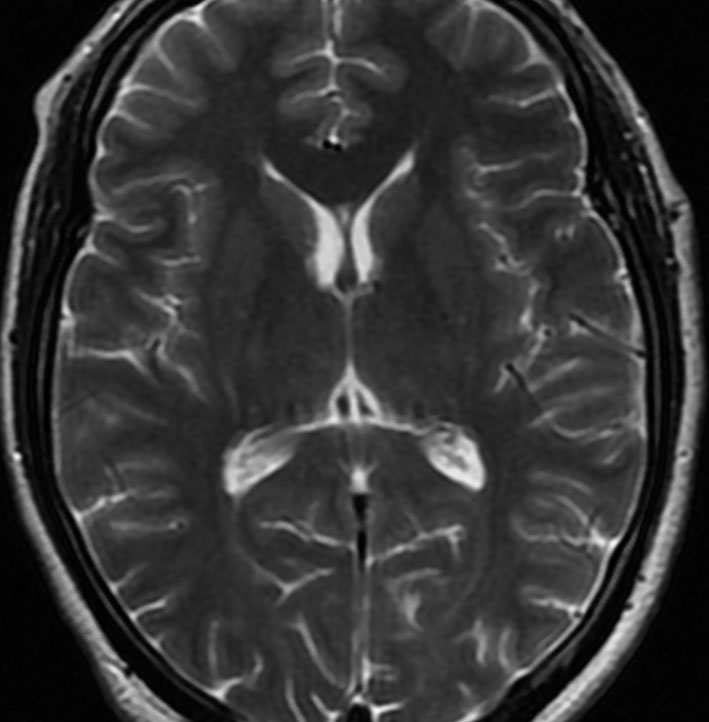

アレビアチン(フェニトイン)やデパケン(バルプロ酸)を何年も服用していると小脳に萎縮がくることがあります。小脳失調症というふらつきがでることは少ないのですが,MRIで小脳が小さくなったようにみえます。

20年以上バルプロ酸の服用をしている患者さんです。左と中央のMRIでは小脳萎縮がありますが,右側の大脳では萎縮は全くありません。小脳症状はありません。